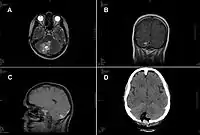

Теніа́зи / Теніїдо́зи (лат. Taeniasis) — під такою назвою в МКХ-10 (В.68) поєднують дві паразитарні інвазії (гельмінтози): таку яку зумовлює бичачий ціп'як (теніаринхоз) і таку, яку породжує свинячий ціп'як (теніоз), при яких зазвичай зараження людини відбувається при вживанні сирого м'яса яловичини або свинини або м'ясних продуктів з них, що інвазовані фінами. При цьому люди є кінцевим хазяїном цих інвазій. При ураженні людини проміжними формами — цистицерками, що можливе при інвазії, яку спричинює свинячий ціп'як, вирізняють окремо як «Цистицеркоз» (В.69). ВООЗ вважає доцільним останнім часом долучати до цієї групи нечисленні випадки захворювання людей Taenia asiatica, які відбуваються виключно в Азії[1]. Їх відносять до В.68.9 «Невизначені теніази».

Ще більш рідкими є ураження людей Taenia crassiceps, описані ураження виключно личинковими формами, через що такі випадки згідно МКХ-10 можна безпосередньо відносити як до «Невизначених теніазів», так і до «Цистицеркозу» (В.69)[2].